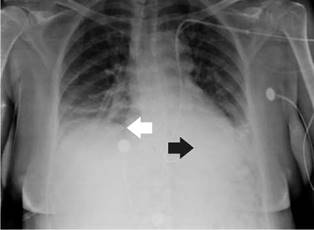

She was diagnosed with cardiogenic shock secondary to non-ST elevation acute myocardial infarction and sinus bradycardia. The initial management in the emergency room, therefore, included dual antiplatelet therapy, anticoagulation, norepinephrine, and dopamine. Then, the patient was transferred to the intensive care unit where a transvenous pacemaker was implanted using the right subclavian anatomical approach with adequate return and no suitable capture. A control chest radiography was performed which revealed no pneumothorax and hemothorax but evidenced the extreme of the pacemaker on the left atrium (figure 1). The pacemaker was considered to be poorly located, so a new one was placed through the left subclavian anatomical approach without complications and adequate capture. However, the team suspected a vascular malformation in the control chest radiograph because the extreme part of the pacemaker was located on the right ventricle (figure 2).

An echocardiogram done showed coronary sinus dilation, which suggests persistent left superior vena cava with the electrode in the coronary sinus dilated. The computed tomography (CT) angiogram showed a superior vena cava on the left that drained abnormally on the left atrium communicating with the right atrium (figure 3). Subsequently, a left cardiac catheterization was performed in another institution on the patient due to myocardial infarction.